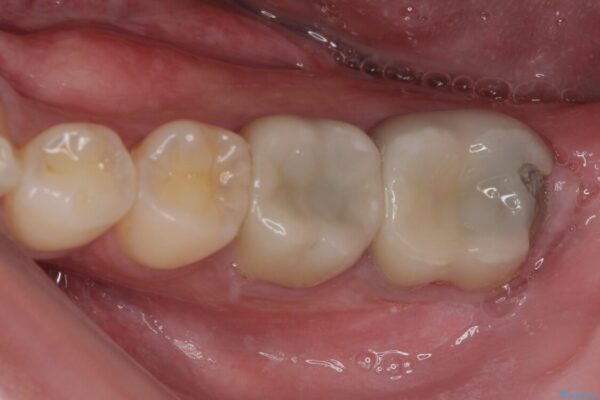

治療前

• 海外赴任前に治したい 割れてしまった奥歯のオールセラミッククラウン 治療前画像